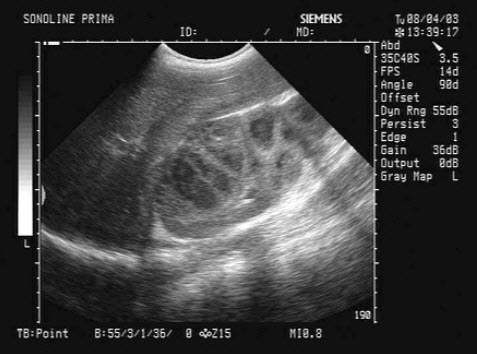

53、单项选择题

根据超声声像图,提示结构为()

A.脐带

B.胎盘

C.胎儿躯干

D.胎儿臀部

E.子宫肌层